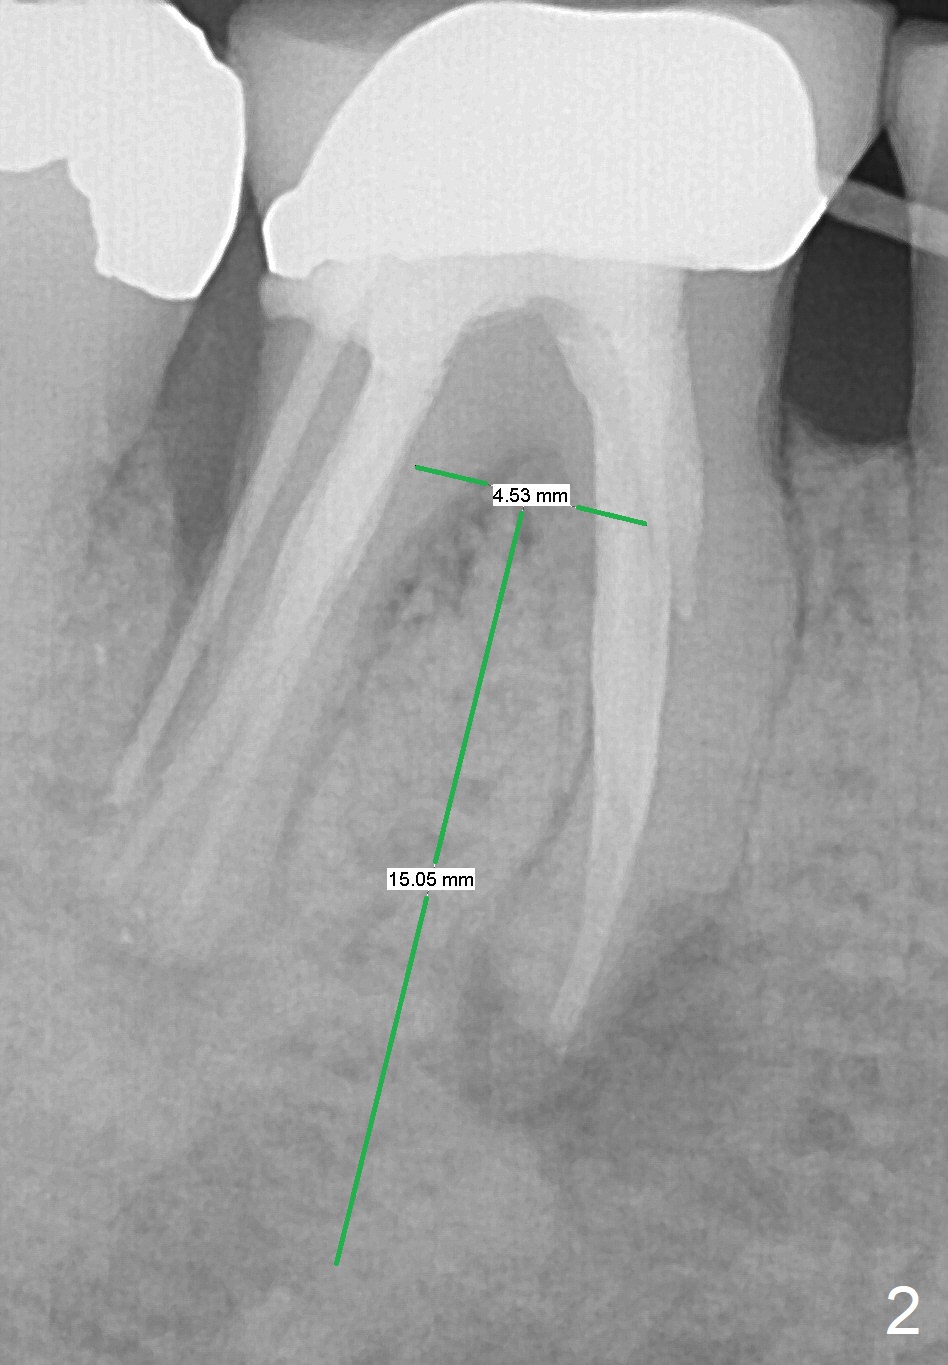

A 79-year-old woman with osteoporosis has pain and buccal swelling 9 years post RCT at #30 (Fig.1 (* gutta percha inserted in fistula)). It appears that the tooth should be replaced by a long implant with better surface treatment for osteointegration (Fig.2). Let the implant heal more than 4 months with progressive loading. Take preop photos to show the buccal infection. For the best trajectory, take PA immediately after 2 mm drill and watch for the deviation of the osteotomy. Place Osteogen plug in the apical portion of the sockets and allograft in the coronal half. Start osteotomy as lingual as possible. The patient is nervous. Comfort her.